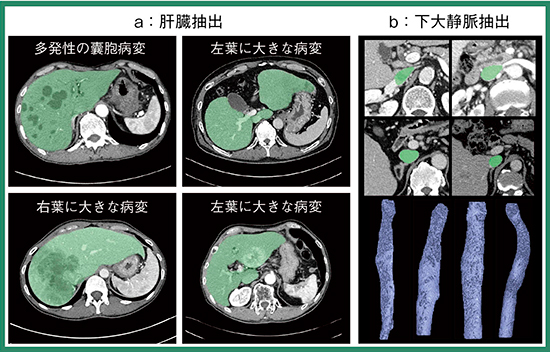

SYNAPSE VINCENTにも,AI技術を用いて設計した機能が搭載されたことで,例えば,“肝臓解析”において従来技術では困難であった疾患のある肝臓も抽出することが可能になった(図4 a)。また,患者ごとに大幅に形状が異なる下大静脈も自動抽出が可能になった(図4 b)。ほかにも,病変の境界が不明瞭な多発性囊胞腎の抽出や,サルコペニアにおける筋肉量の測定も行えるようになった。

図4 肝臓・下大静脈抽出